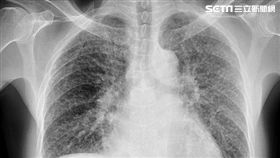

肺部「毛玻璃」影像嚇壞 醫:不等於癌症

隨著低劑量電腦斷層掃描(LDCT)被廣泛納入健檢項目...

獨/她不菸、少煮菜 「1原因」肺部滿天星

肺癌是國人十大癌症中死亡率最高、新增人數最多的癌症。...

沒有不舒服!50歲男健檢照出上百顆肺結節

從事高風險職業,定期健檢很重要!胸腔科醫師蘇一峰分享...